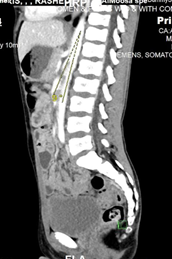

Fig 4: Sagittal image of IV contrast enhanced CT scan of the abdomen demonstrates aortomesenteric sharp angle ( 9°) (Normal range > 22°).

The tight and sharp aortomesenteric distance and angle respectively along with the gastric and duodenal dilatation are in favour of superior mesenteric artery syndrome.